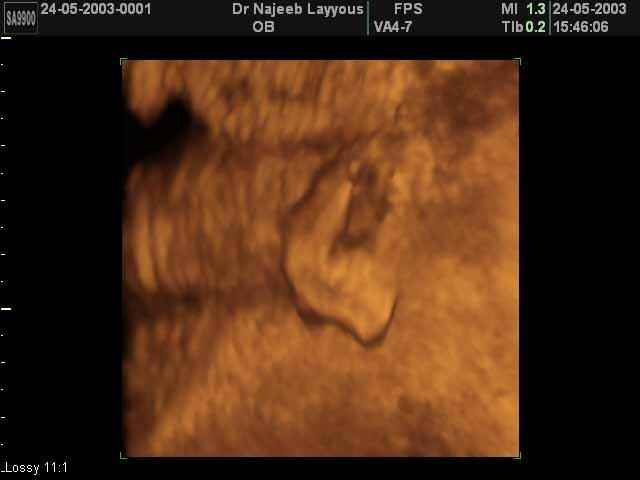

- Fetal Parts Ultrasound Scan Photos